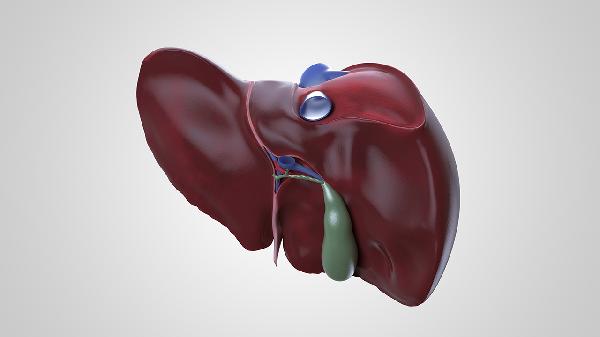

丙肝治愈后复发的可能性较低,但需定期监测肝功能以排除潜在风险。治疗丙肝主要依赖抗病毒药物,如索磷布韦、达卡他韦和利巴韦林,这些药物能有效清除病毒,降低复发率。治愈后,保持良好的生活习惯和定期复查是关键。

1、丙肝治愈后复发的原因可能与病毒未完全清除或再次感染有关。尽管抗病毒治疗能清除大部分病毒,但极少数情况下,病毒可能隐藏在肝细胞中,导致复发。再次接触感染源,如不洁注射或输血,也可能引发复发。

2、定期监测肝功能是预防复发的重要手段。通过检测肝功能指标和病毒载量,可以及时发现异常。建议每6个月进行一次肝功能检查和病毒载量检测,确保病情稳定。